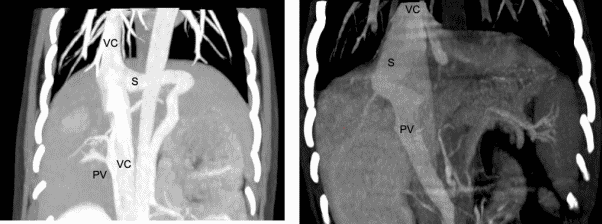

Diagnostic imaging is necessary to identify the shunt in order to confirm the diagnosis and to rule out other causes of liver dysfunction. It also provides important information on the location and morphology of the shunt to allow appropriate treatment. Abdominal ultrasonography is useful as a screening tool and may provide sufficient information on the nature of the shunt for surgical planning. Although convenient, ultrasound is very operator dependent, and the accuracy is therefore variable. Computed tomography angiography (CTA) is recommended as the gold standard for imaging CPSS and provides a wealth of information on the location and morphology of the shunt as well as the degree of portal vasculature development. It is minimally invasive and can be performed safely prior to surgery but is relatively expensive and does require sedation or anesthesia. In our experience, ultrasonography, performed by an experienced operator is sufficient to diagnose a shunt and allow surgical planning in most animals with extrahepatic CPSS.

(right). S = shunt, PV = portal vein, VC = vena cava